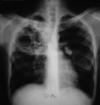

Use these for diagnosis of what?

- Radiographically presents with nodular, irregular, pleural thickening, poss pleural effusion, and pleural plaquing

- CXR

- CT

- Thoracentesis

- Surgical biopsy

- Usually necessary for diagnosis

- Difficult to diagnose

- PET

- Helpful in ?malignancy; staging; poss surgical candidate

Mesothelioma